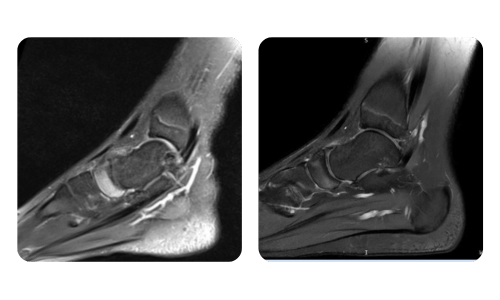

Progresul pacienților noștri, măsurat înainte și după terapia hiperbară, reflectă eficiența și impactul pozitiv al tratamentului. Descoperă rezultate documentate ale terapiei hiperbare la clinica Hyperbarium Oradea, bazate pe evaluări clinice și date obiective care evidențiază îmbunătățiri semnificative în diverse afecțiuni.